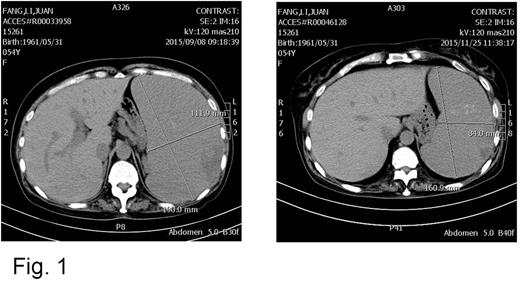

After two cycles, the bone marrow smear showed the blasts was decreased to 0.5%, and abdominal CT showed the spleen was shrank (Fig.1). After four cycles, she felt comfortable and the peripheral blood count was improved towards normal. The treatment interval was prolonged. After 8 cycles, the spleen reduced to 2cm under rib, and hematological remission was achieved. After 10 cycles, the mutation of JAK2/V617F expression was decreased from 60.63% to 0.01%. During the therapy, the patient presented grade III-IV hematological toxicity at first two cycles, and there were no side effect happened at following cycles.